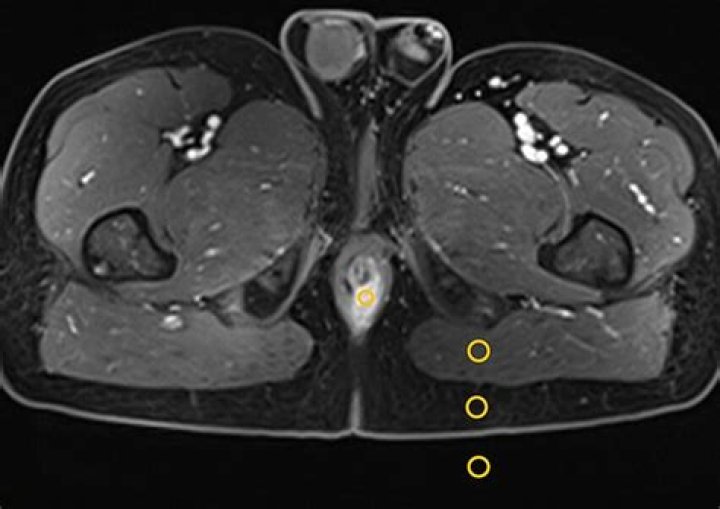

What is CNR MRI?

CNR (contrast-to-noise ratio) is a measure of how distinguishable two structures are from each other. For magnitude images (most commonly used in MRI), the. contrast-to-noise ratio is: CNR = SNR, – SNR. – 0.655.(S, -S2)

Contrast-to-noise ratio (CNR) is just the ratio of the estimated contrast and noise: CNR = C/N.